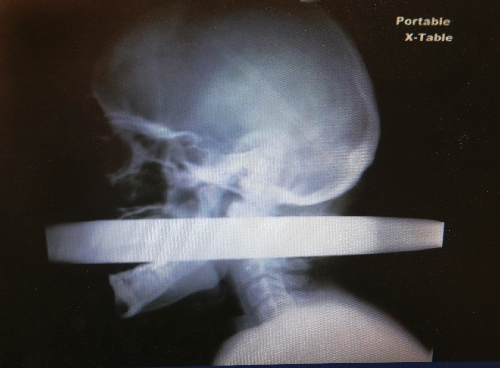

Seeing the miracle of episodic analgesia

As Andrew Linn sat on a gurney with 4 inches to 6 inches of pole sticking out of his mouth and neck — the 2-inch-diameter metal had been driven through his mouth and out through his neck in a Las Vegas auto accident, he took out his phone and began to text his wife about what had happened.